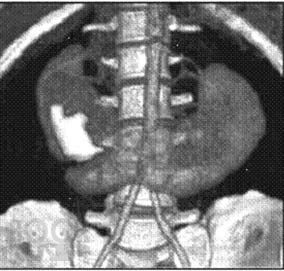

Аномалии развития почек: диагностика и лечение

Изложены вопросы этиологии, патогенеза, классификации, диагностики и лечения аномалий развития почки. Отдельным разделом представлены сведения о кистозных образованиях почки, как наиболее частых заболеваниях почечной структуры, имеющих тенденцию к злокачественному перерождению и требующих дифференциальной диагностики с онкологическими процессами в почке. Детально освещены диагностика и современные малоинвазивные методы лечения простых кист.